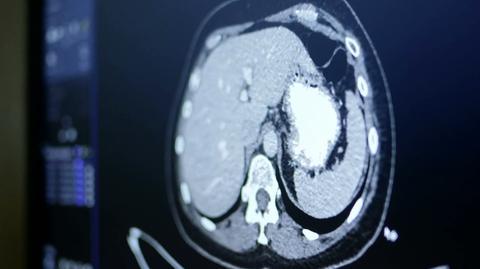

Onkologia w czasie pandemii. Chorzy czekają na planowe zabiegi, lekarze mówią o katastrofie, a minister o "zielonej wyspie". Dużo w tym emocji i nerwów, co pokazał spór o respiratory na Mazowszu.

Po tym, jak Konstanty Radziwiłł nakazał w Instytucie Gruźlicy i Chorób Płuc w Warszawie zwiększyć liczbę łóżek respiratorowych dla pacjentów z COVID-19, placówka musiała odwołać planowe zabiegi. Zabiegi ratujące życie, bo jako jedyne dające szansę na wyleczenie chorym z rakiem płuc. O sprawie jako pierwszy napisał "Wprost".

- To, że w tej chwili te decyzje, dotyczące przesuwania zabiegów, dotykają pacjentów onkologicznych, dla nas jest jednoznacznym sygnałem, że mamy w tej chwili katastrofę - uważa profesor Piotr Wysocki, kierownik Oddziału Onkologii w Szpitalu Uniwersyteckim w Krakowie.

Konflikt na Mazowszu zwrócił uwagę na jeszcze jedno - problem pacjentów onkologicznych niemal w całym kraju, którzy wbrew słowom wojewody mazowieckiego, że "onkologia jest chroniona", wciąż dotkliwie odczuwają skutki pandemii.

- W onkologii również widzimy opóźnienia, przesunięcia, nie do końca adekwatny strandard postępowania właśnie z uwagi na pandemię - tłumaczy profesor Piotr Wysocki.